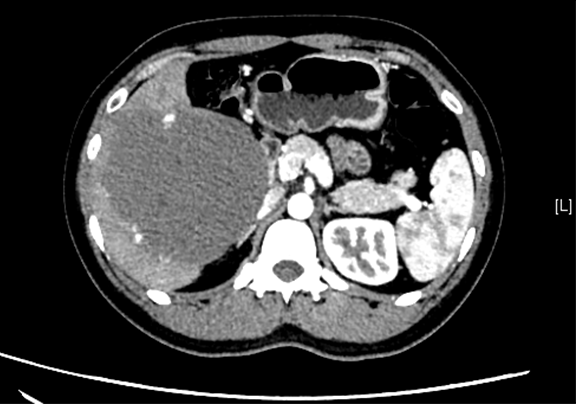

辅助检查: 下腹部增强CT示:肝右叶巨大占位。

术前CT检查:动脉期

静脉期

平衡期